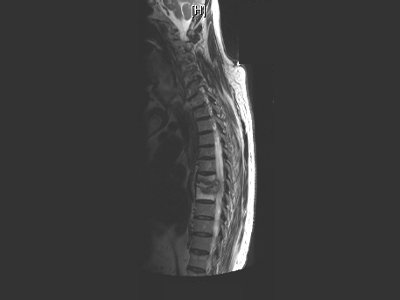

Columna cervical